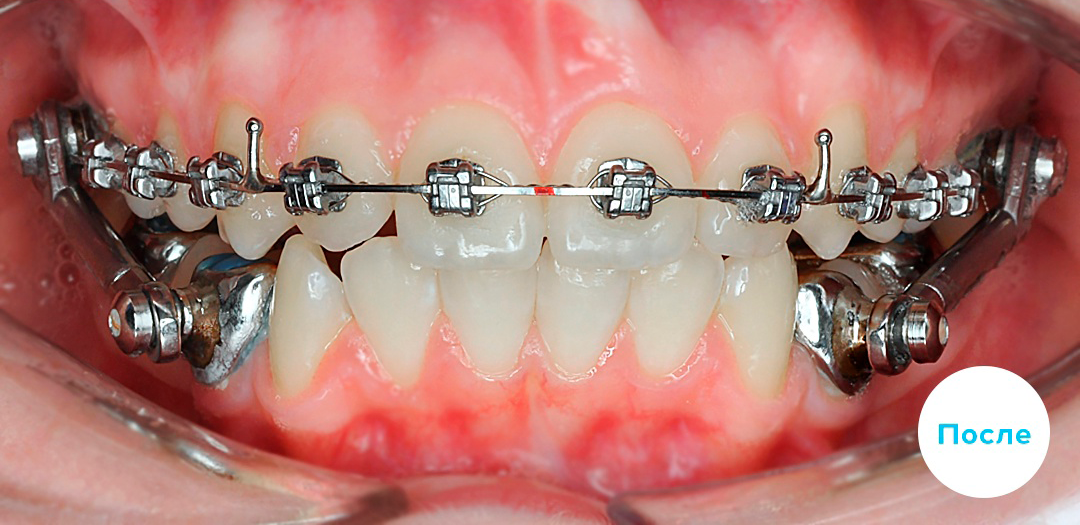

Металлические брекеты — классическая ортодонтическая система для исправления прикуса, выравнивания зубов и коррекции положения зубных рядов. Несмотря на появление керамических и сапфировых систем, металлические остаются одними из самых востребованных. Их выбирают за прочность, надежность, предсказуемую биомеханику и возможность эффективно работать даже в сложных клинических случаях.

Это несъемная ортодонтическая конструкция, которая фиксируется на зубах и постепенно перемещает их в правильное положение. В ее основе — замочки, ортодонтическая дуга и дополнительные элементы, которые создают направленное давление и помогают последовательно выравнивать зубной ряд.

Принцип работы металлических брекетов основан на постоянном контролируемом воздействии на зубы. После фиксации дуга стремится вернуться в заданную форму и за счет этого постепенно перемещает зубы. Лечение идет поэтапно и требует регулярного контроля у ортодонта.